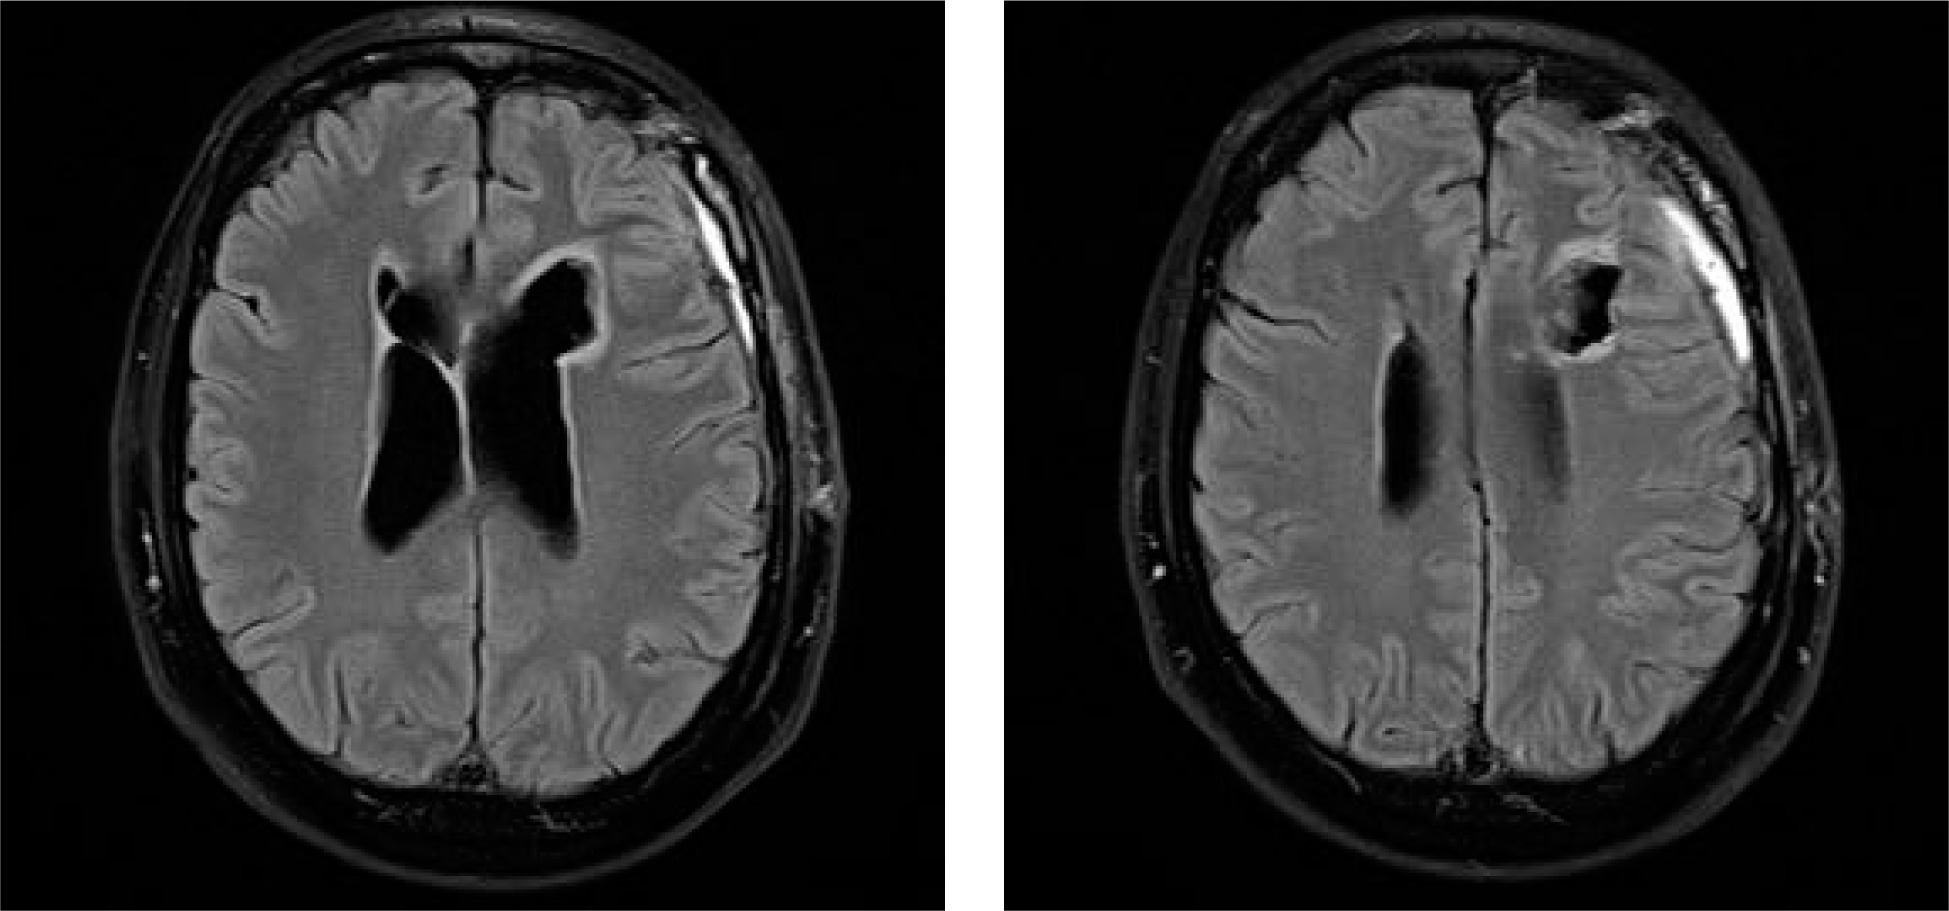

An MRI scan showed an irregular mass in the frontal horn of the left lateral ventricle and a nodular lesion with a cystic appearance in the frontal horn of the right lateral ventricle (Figure I). The maximum size of the cysts was approximately 46 mm, with a solid portion of 43 mm. The tumor was hyperintense with variable contrast enhancement. The tumor mass was shown to compress the foramen of Monro, resulting in an enlargement of the lateral ventricles.

Figure I

Subependymoma. Preoperative MRI image showing an intraventricular tumor arising from the ventricular wall. Axial post-contrast T1 imaging

Follow-up imaging obtained 3 weeks after surgery demonstrated an irregular emptying postoperative cavity within the left frontal lobe and moderately dilated ventricular system. On the right side of the ventricle, below the frontal horn, there was an irregular fluid space with a maximum dimension of approx. 11 mm, most likely an infract cavity (Figure V). The patient’s postoperative functioning is currently stable. There are no reported or observed functional impairments or limitations at this time. The patient is displaying normal cognitive and physical abilities, and there have been no indications of any neuro-psychological deficits or abnormalities in their assessment. At the 4-year follow-up after the neurosurgical operation imaging was unremarkable. It is essential to continue monitoring the patient’s progress and conducting regular follow-up assessments to ensure his ongoing well-being.